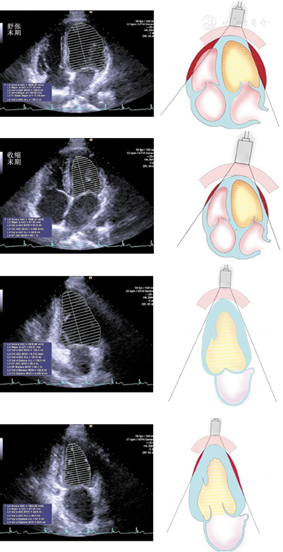

图2

胸骨旁左心室长轴切面,显示二维超声心动图舒张末期左右心室壁厚度、室间隔厚度和左右心室内径测量方法